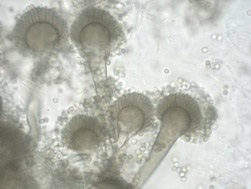

Aspergillusfumigatus. Mikroszkóp tiszta tenyészet.

A micélium A. fumigatus nazális mosófolyadékot (fluoreszcens mikroszkópia).